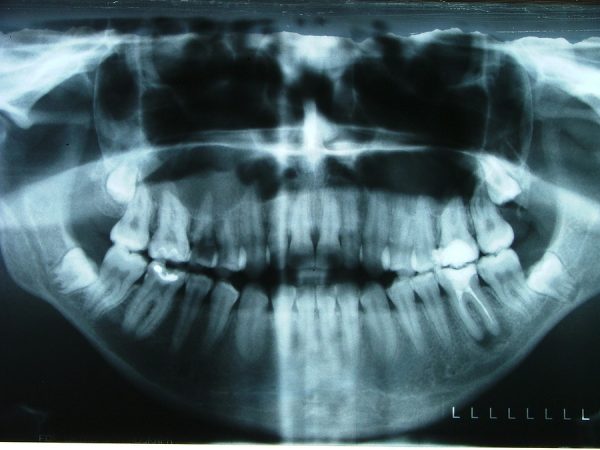

Auf keinen Fall sollten Betroffene allein herumdoktern, da dies den Zustand weiter verschlimmert. Oftmals suchen die Betroffenen aufgrund von starken Schmerzen einen Zahnarzt auf, der durch

- Röntgen,

- MLP und

- CT

zunächst eine Diagnose erstellen. Eigentlich gelten alle Behandlungsschritte nur einem Ziel, den Entzündungsherd zu beseitigen. Aus diesem Grund setzen die ersten Symptome auf eine breit gefächerte Behandlung, die gleich mehrere Bereiche anspricht.